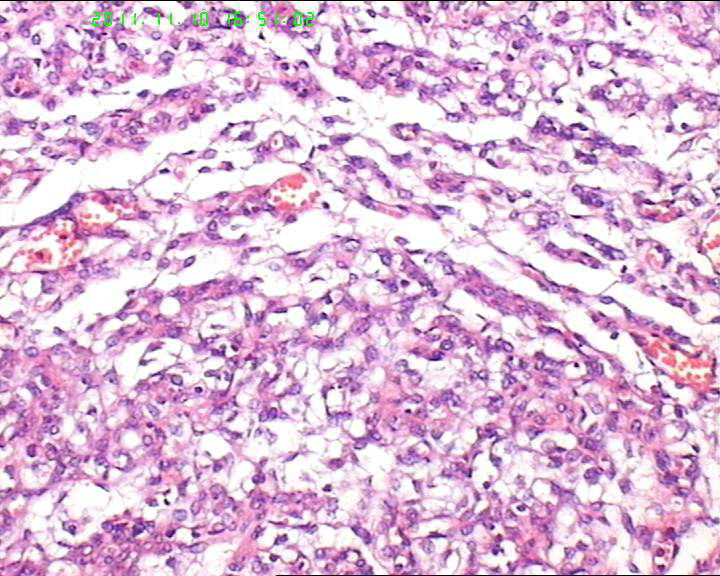

19岁,停经33周,前置胎盘,剖宫产。胎盘母体面可见一灰褐色结节,直径约5.5cm,包膜完整,切面实性,质略嫩。

典型的绒毛膜血管瘤

典型的胎盘毛细血管瘤,发病率约1%,前一阵刚遇到一例。

毛细血管瘤,胎盘常见的肿瘤